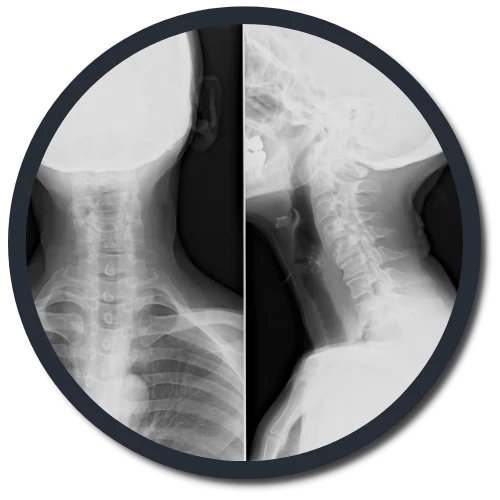

Eternal Hope Chiropractic uses the Gonstead method of adjusting and analyzing the spine. We're one of a few offices in Middleton that exclusively uses the Gonstead method. By thoroughly analyzing the spine through the use of x-ray, instrumentation, visualization, static and motion palpation you can expect a properly delivered adjustment.